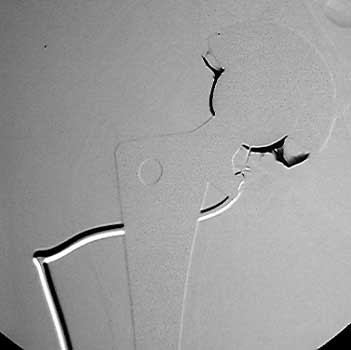

Arthrographic evidence of loosening—contrast enters

abnormally widened interface Gruen zone 1 and 2

Arthrographic evidence of cup loosening—contrast enters

abnormally widened interface Gruen zone II and III